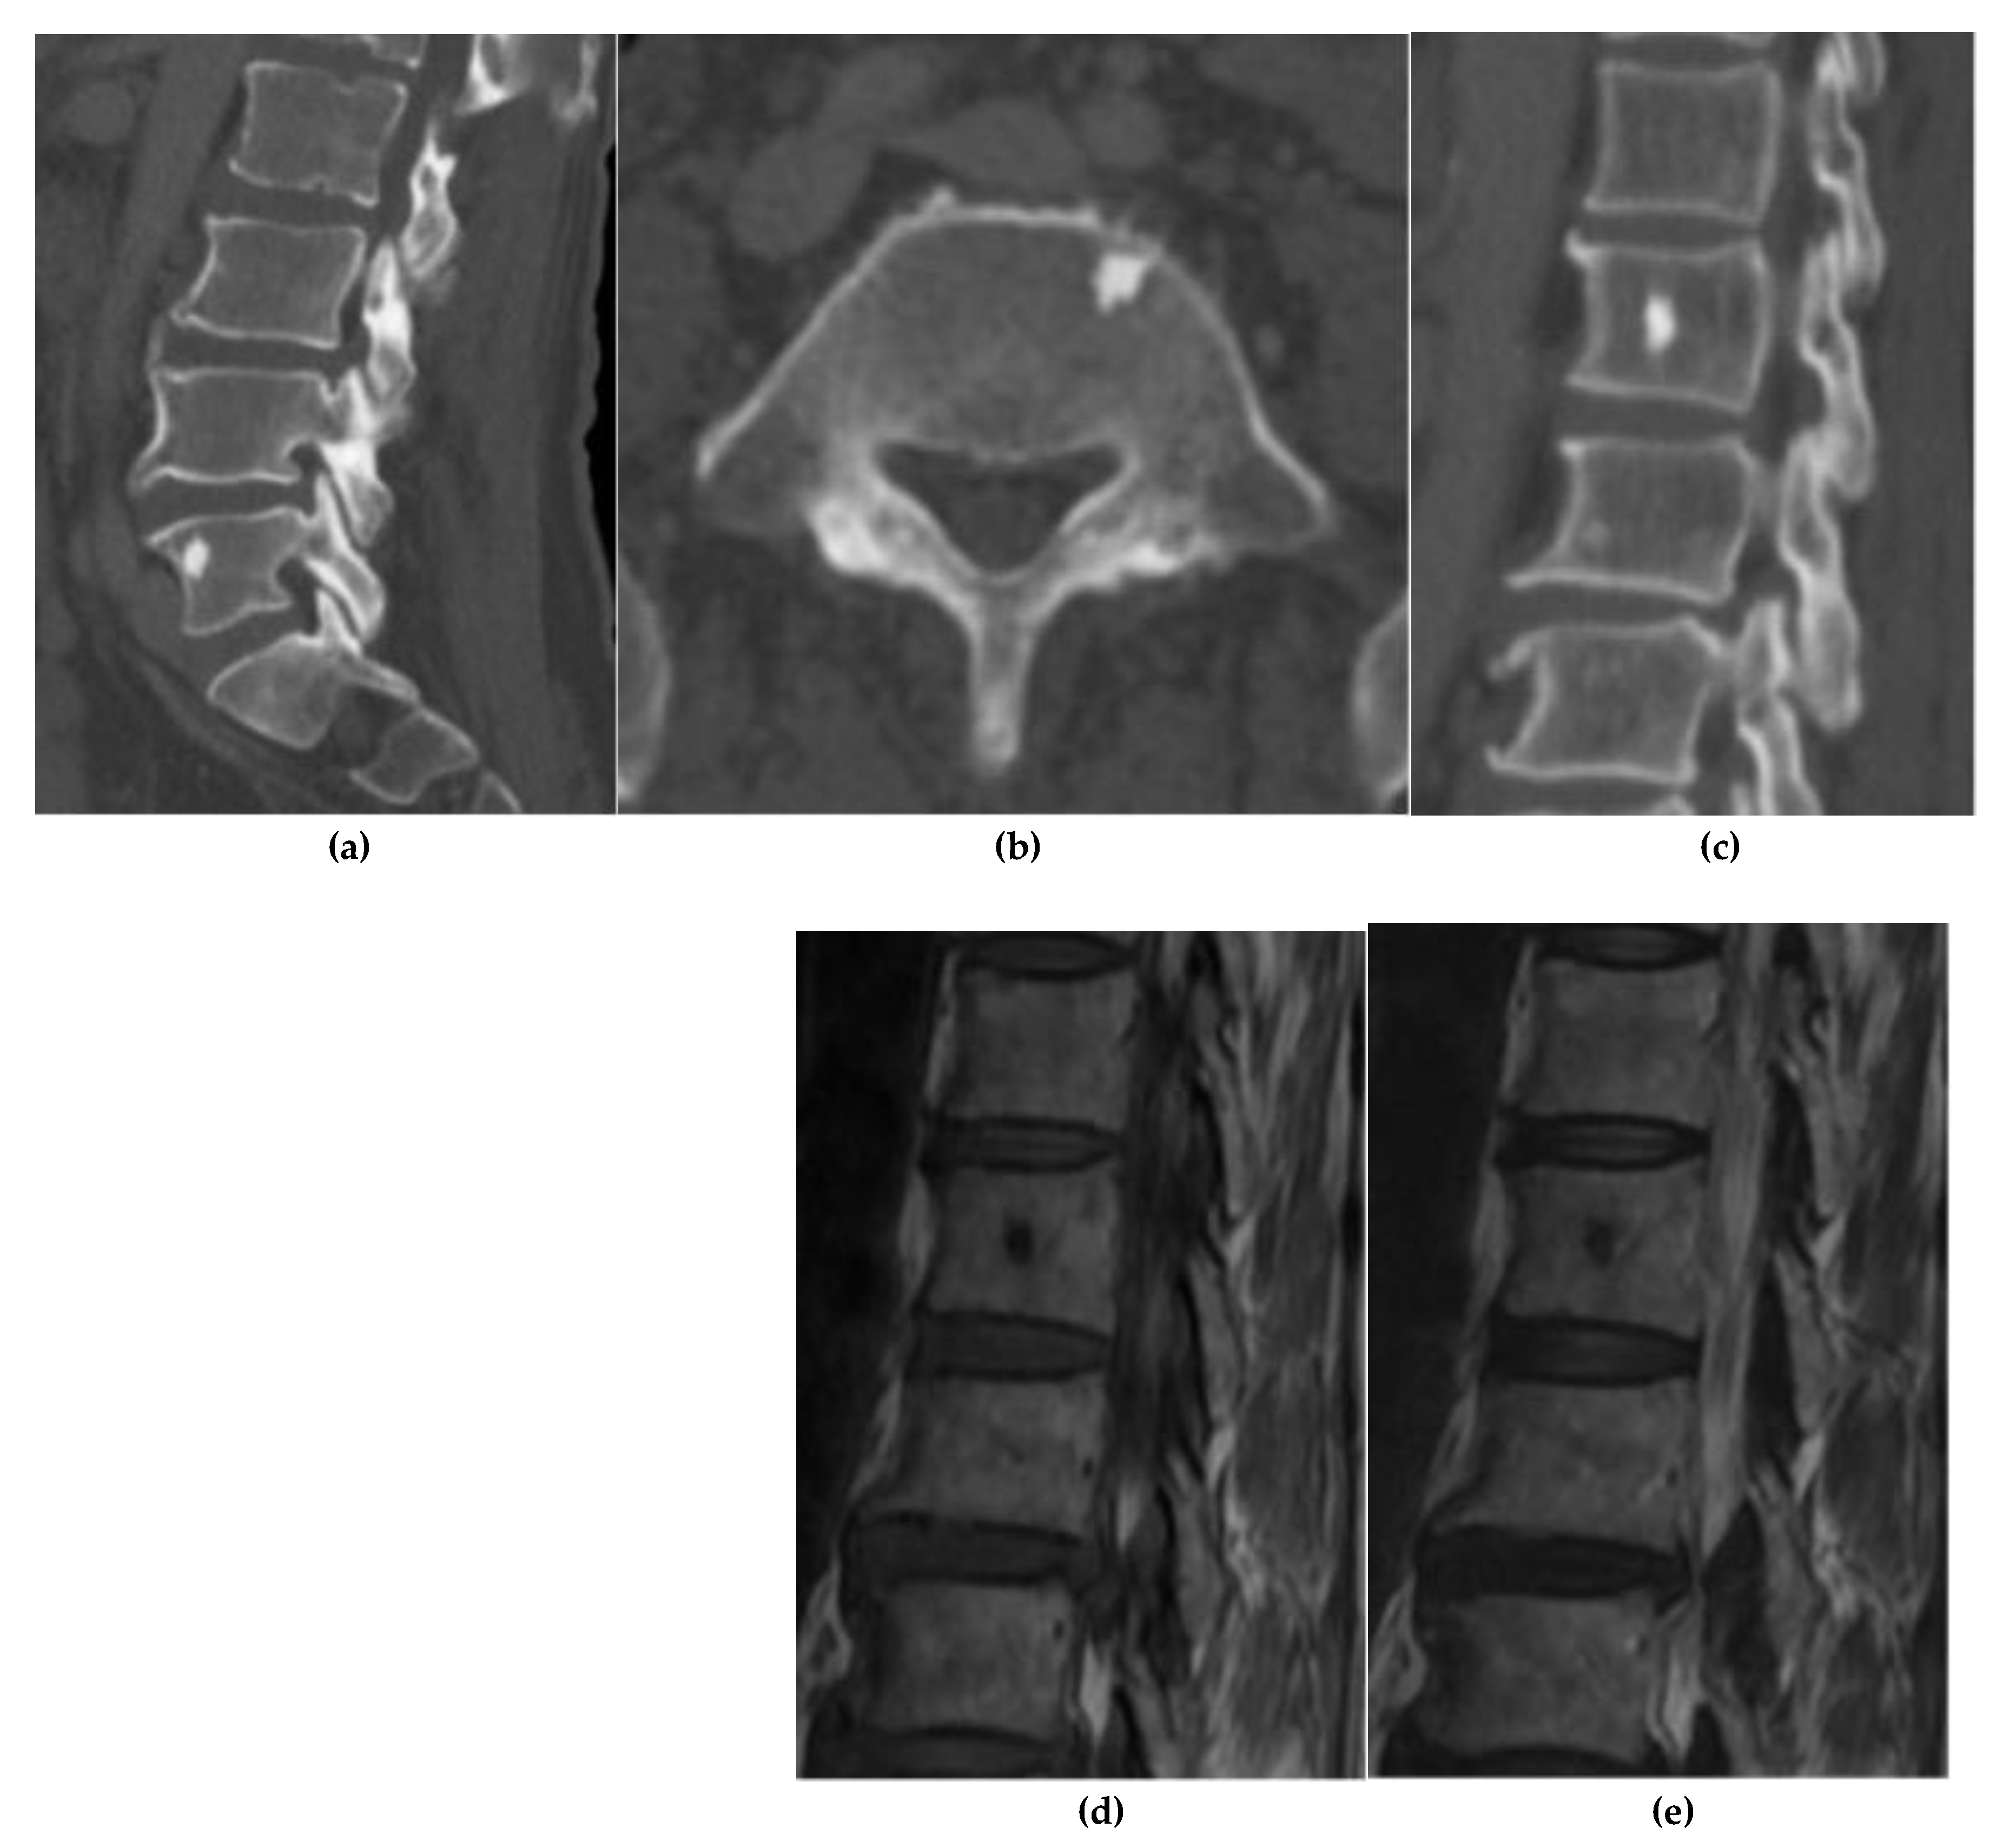

Osteoid Osteoma

Osteoblastoma